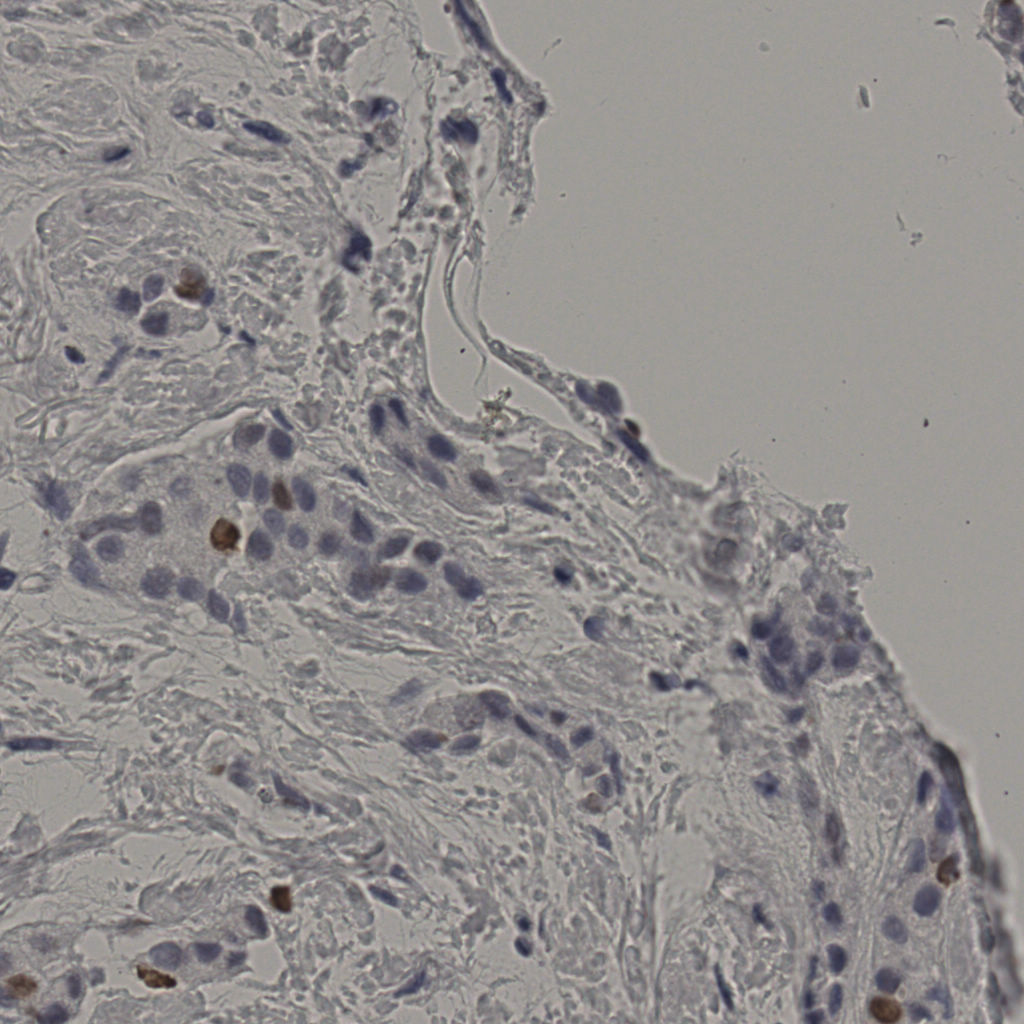

5.31%

Ki67 指数

阴 19502 阳 1093